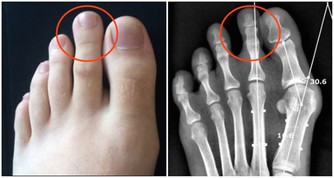

四、骨骼強壯,聽力好

腎主骨,骨靠腎精滋養,腎好骨才好,同時在出現耳鳴耳聾聽力下降一般就有可能是因為腎陰虛導致。